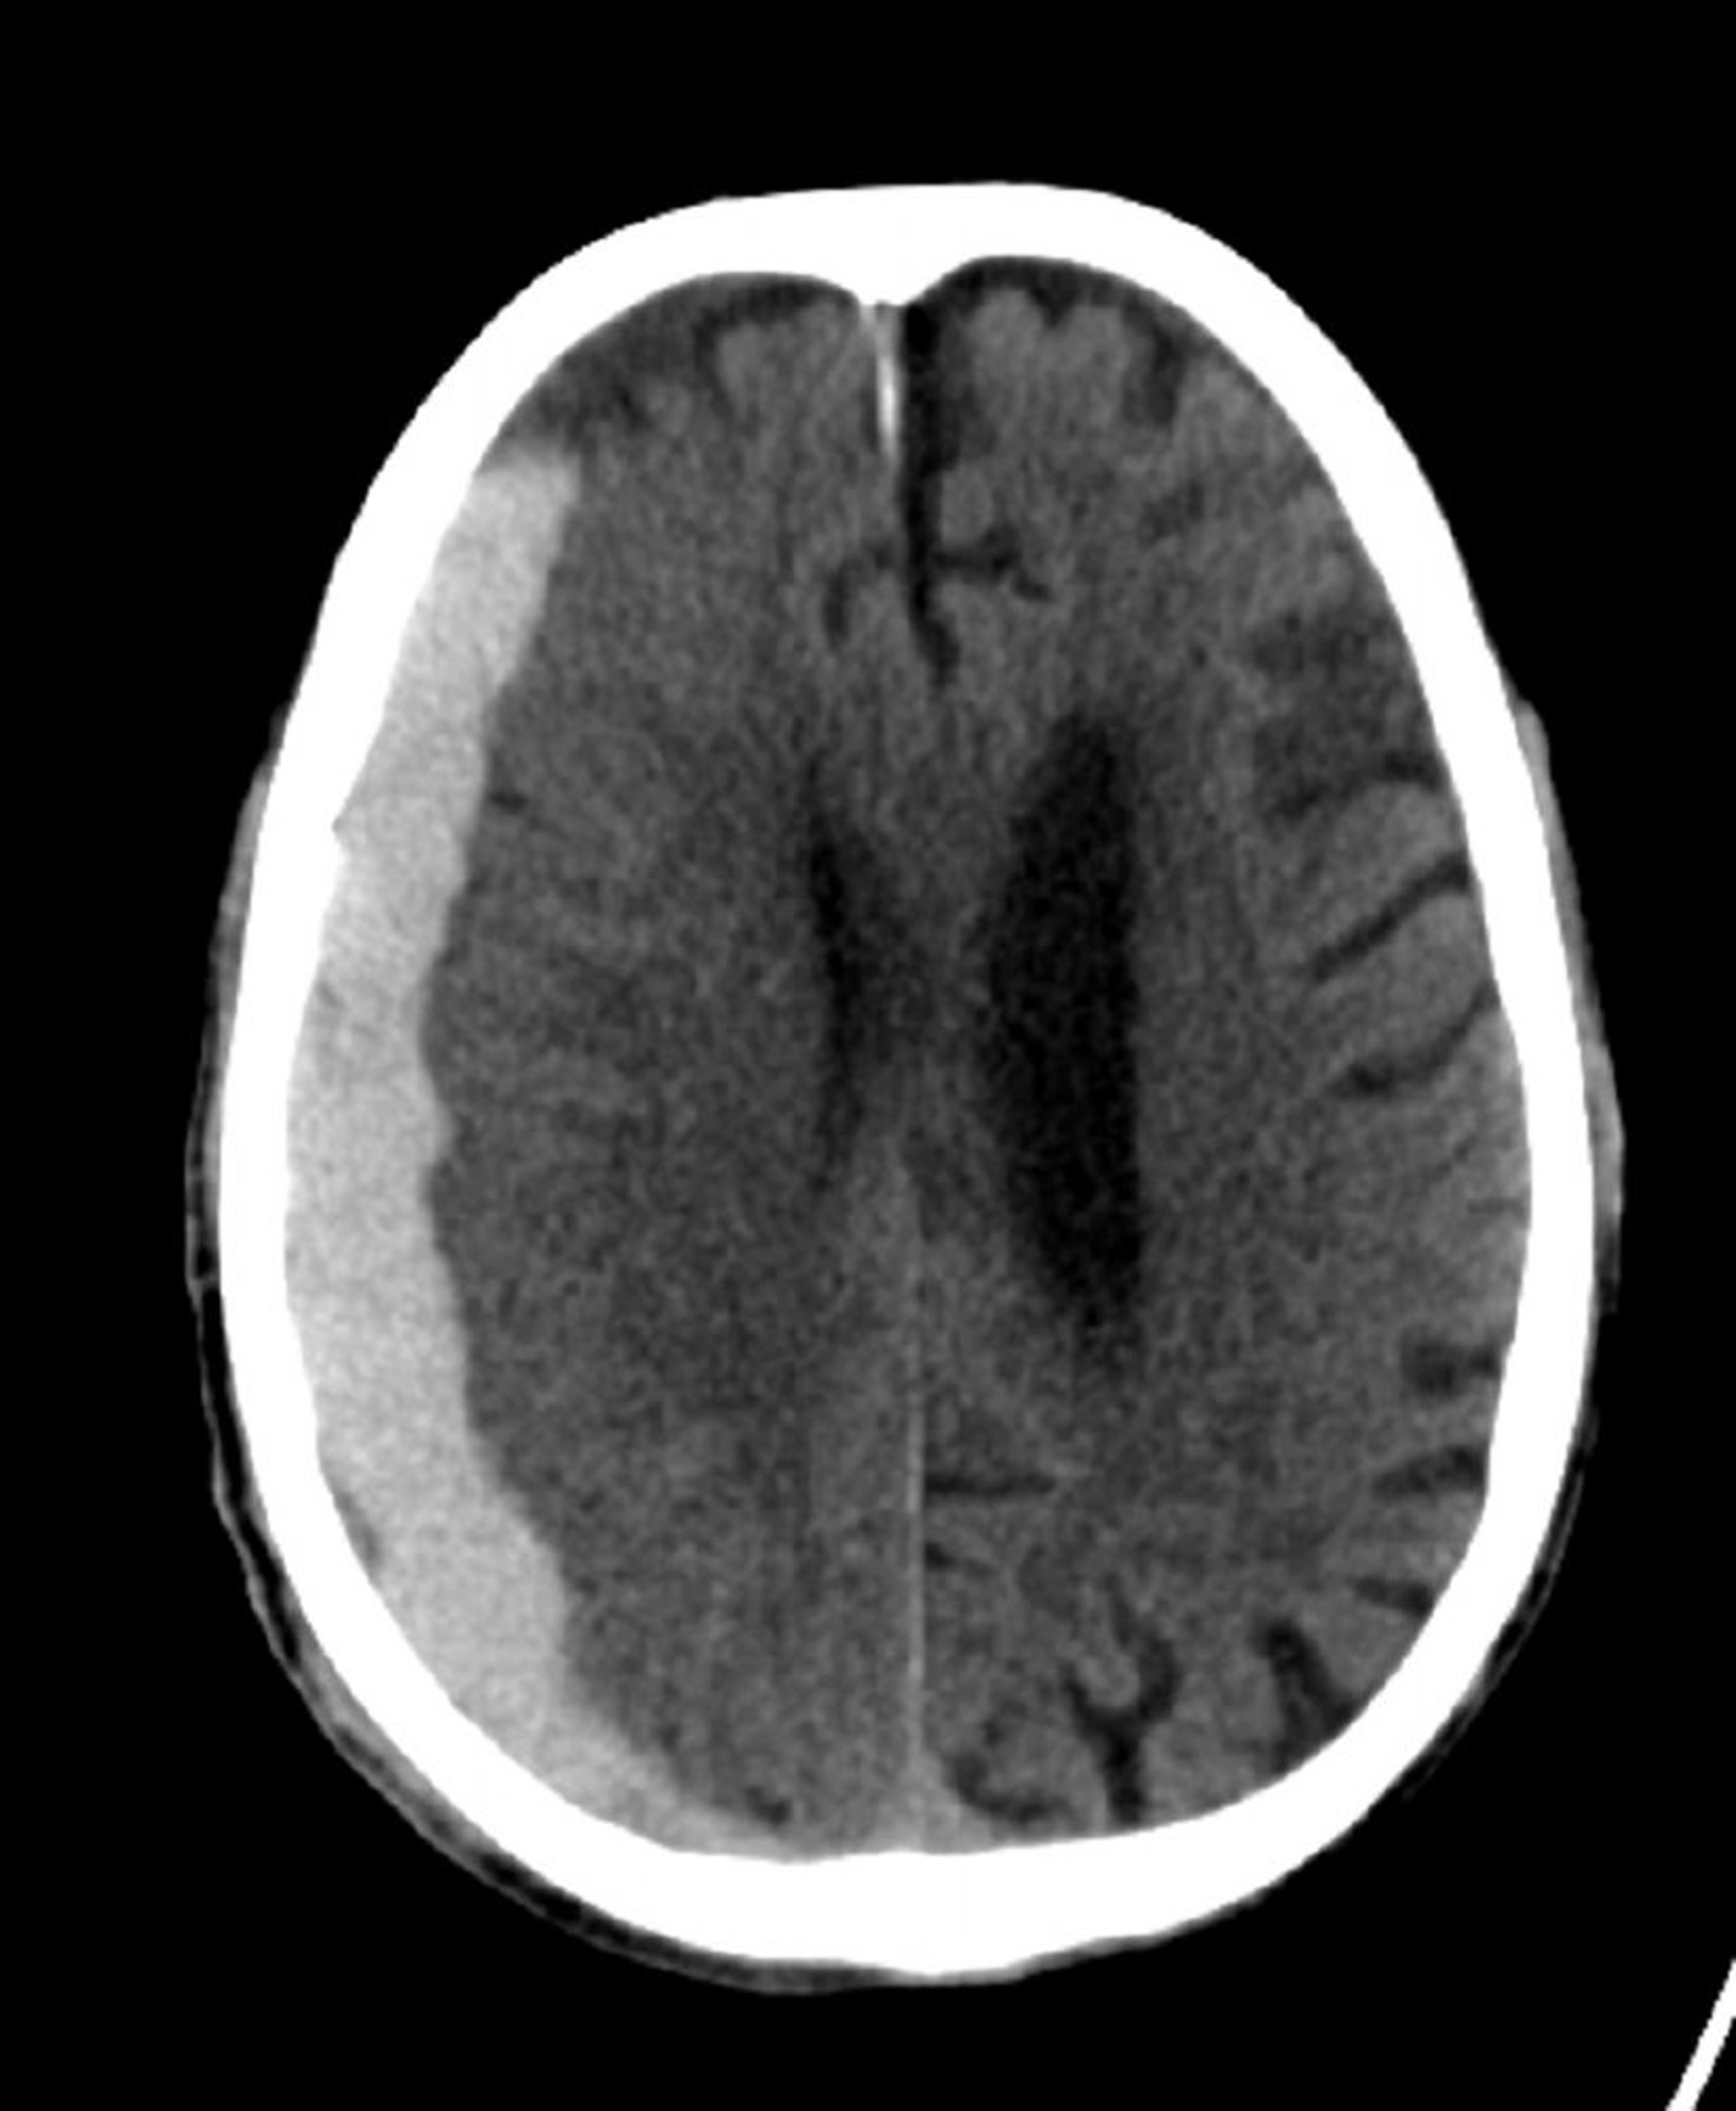

硬膜下出血(CT)

縫合線を越えて進展している古典的な三日月形の高吸収域。

© 2017 Elliot K.Fishman, MD.